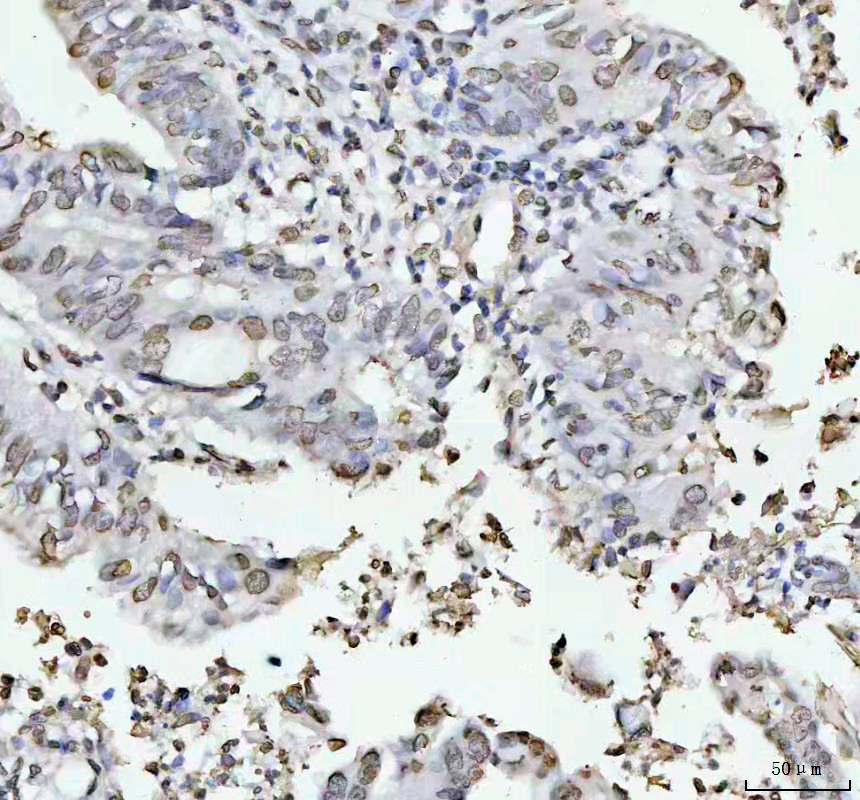

IHC analysis of Histone H4 using anti-Histone H4 antibody (BM4713) .

Histone H4 was detected in a paraffin-embedded section of human breast cancer tissue. The tissue section was incubated with rabbit anti-Histone H4 Antibody (BM4713) at a dilution of 1:200 and developed using HRP Conjugated Rabbit IgG Super Vision Assay Kit (Catalog # SV0002) with DAB (Catalog # AR1027) as the chromogen.